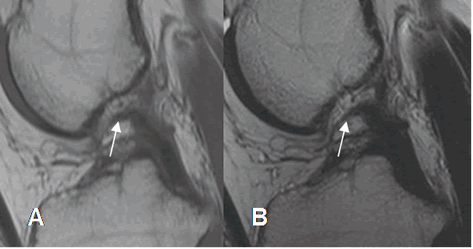

Fig 114. Ruptura del LCP.

A: RM sagital en T1 y B: RM sagital en T2. Solución de continuidad del LCP en su tercio proximal, por ruptura.